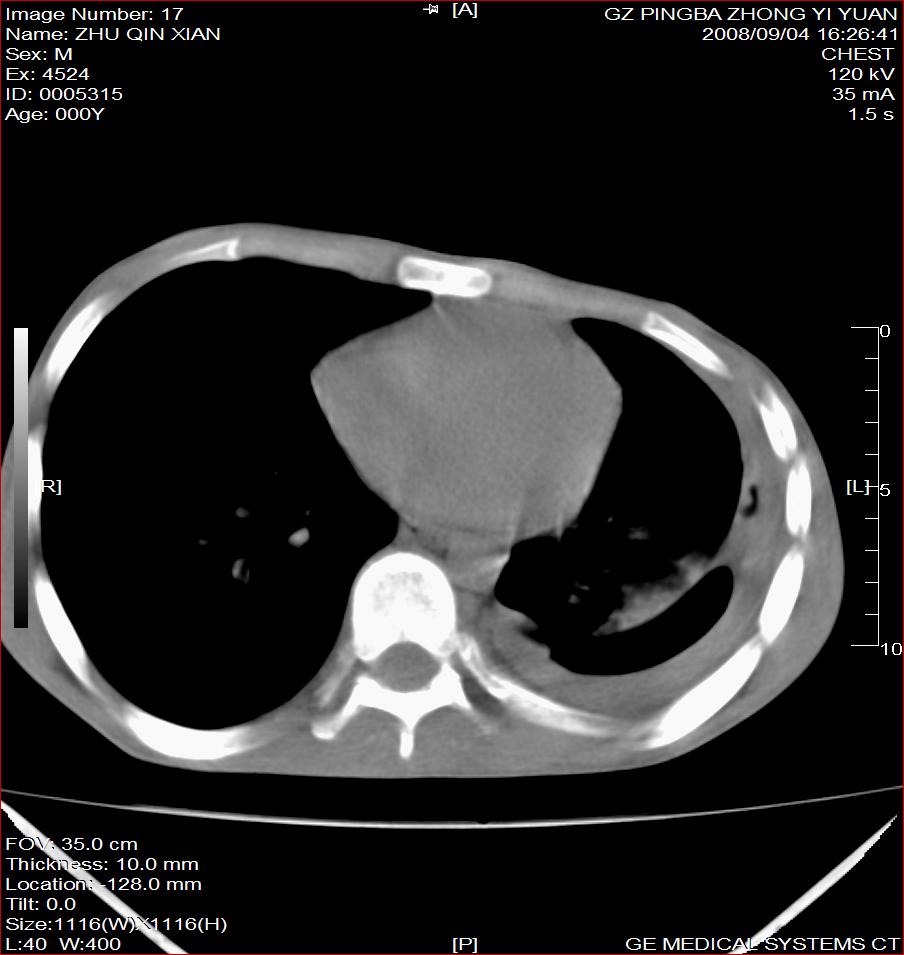

以下是引用随光逐影在2008-9-4 20:05:00的发言:[br]1)考虑两肺结核。2)左侧胸膜炎(胸膜肥厚、粘连,胸腔积液)。3)左侧局限性气胸。

以下是引用子十在2008-9-4 19:34:00的发言:[br]左上肺结核并空洞及双肺播散。节段性肺不张、胸腔积液、胸膜肥厚粘连。[br]